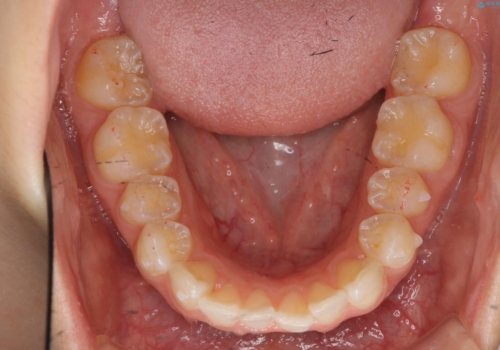

前歯のがたつき インビザラインで

- 前歯のがたつきを治したいとのことでした。歯を抜かずにできる範囲で引っ込めたいとのことでした。

歯列の側方拡大(横に広げる)と、エナメル質の削合で並べました。

歯を抜いているわけではないので、口元はそこまで変化はありませんが、前に出すことなくデコボコは取れたと思います。